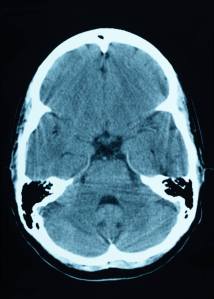

Brain CT scan

As a hospitalist, I see 10 or 20 brain scans every week.  A healthy 40-year-old brain nicely fills out the allotted space in the skull.  Most 70-year-old brains have an obvious degree of shrinkage.  Those with the most shrinkage typically have worse mental functioning, often diagnosed clinically as dementia, or its precursor, mild cognitive impairment (MCI).

The medical term for brain shrinkage is brain atrophy.  It reflects loss of brain cells or decrease in brain cell size.  I see A LOT of atrophied brains and impaired mental functioning—aka diminished cognition—in the elderly.

Not everybody with atrophy has mental impairment; healthy brains slowly atrophy with age.  Alzheimer’s disease patients atrophy quickly; MCI patients atrophy at an intermediate rate.  MCI patients converting over the years to Alzheimer’s show a faster rate of atrophy.